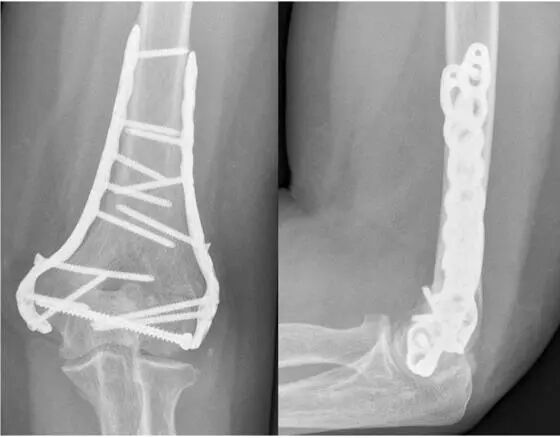

肘部骨折约占成人骨折的7%, 肱骨远端骨折占所有肘部骨折的 30%。当需要切开复位内固定 (ORIF) 时,会出现多种手术并发症,其中之一,为尺神经病变。Slobogean指出手术治疗移位的肱骨髁上骨折后医源性尺神经损伤汇总风险差异为0.035(95%置信区间,0.014-0.056)(8)。尺神经病变是一个独特的挑战,因为它可能是初始损伤、手术治疗或术后康复的产物。肱骨远端骨折ORIF后尺神经病变的发生率在 0% 和 51% 之间。目前尚不清楚在ORIF期间除了尺神经原位或转位管理尺神经的最佳方法是什么。(7)

有人认为前置的优势在于不仅能够避免其受到内置物、骨痂形成的激惹和压迫,而且增加了尺神经活动的空问,减轻肘关节屈曲对尺神经的牵扯,从而减少尺神经炎发生,更有利于时关节功能的恢复(1)。但Abdulaziz F指出在没有预先存在神经病变的肱骨远端骨折的ORIF期间,尺神经转位与没有转位相比,发生尺神经神经病变的风险几乎是五倍。尺神经神经病变的风险不受其他混杂因素的显着影响。因此,不建议在肱骨远端骨折ORIF期间进行常规尺神经转位(2)。

在篇有关尺神经是否前置的meta分析中,作者指出,与原位治疗相比,接受转位治疗的患者术后尺神经病变更为普遍。在此过程中尺神经转位没有保护作用,而原位释放可能更有利(3)。但刘刚等人指出手术入路中肱三头肌两侧入路相对于鹰嘴截骨入路、钢板放置方式中钢板平行放置相对于垂直放置,为术后尺神经功能障碍发生的危险因素,尺神经前置与非前置并没有统计学的差异(4)。如果不是术中特别需要,一般不太建议尺神经的前置。

尺神经前置适应症

蔡俊,王玮等人认为尺神经原位时不影响内固定物的放置,张力无明显增加、位置稳定、无滑脱表现,则不做尺神经前移,如果出现尺神经沟处骨组织已经破坏、内固定物放置时影响尺神经原有解剖位置、预计骨痂或瘢痕形成会造成神经受压等因素,则建议行尺神经前置术。(5、6)。

尺神经前置技术特点

尺神经前置:近端游离尺神至Struthers弓,远端尺神经游离至尺骨起始部的腱膜和尺侧腕屈肌,要特别注意保护尺侧腕屈肌的肌支。注意保护尺神经在肘部的血供。当尺神经彻底松解后可前移,但新的尺神经床要宽敞以免新的卡压。范存义等人认为尽量要筋膜下前置尺神经(9)。不前置者不需长距离游离尺神经,尺神经无张力放置原位,但需保证原有活动空间,关闭切口前需屈伸肘关节测试尺神经松紧度(5、6)。